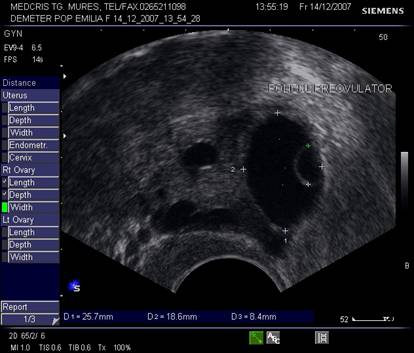

Dupa ziua a 5-7, un folicul ovarian devine dominant , fata de ceilalti ce devin atretici. In ziua 10 -a - 11-a foliculul depaseste 12 mm diametru. Cresterea foliculara de 2 - 3 mm/zi ne duce la un folicul preovulator de cca 21 mm diametru (24 - 26 mm). Doi foliculi dominanti au fost identificati in 10% din ciclurile spontane [8].

Deoarece foliculii sunt ovoidali, diametrul mediu conteaza pentru foliculometria, dupa masurarea a 3 diametre si impartirea la 3.[6]

Semnele ecografice ale ovulatiei iminente [6,9]:

Ovarul:

diametrul folicular peste 20 mm,

detectarea cumulus oophorus in folicul

semnal Doppler la periferia foliculului

Fig. nr.371. Folicul selectat ziua a XI a de ciclu menstrual, la ecografia transvaginala

Fig. nr.372. Folicul preovulator , in care se remarca

cumulus oophorus ( sageata, eco transv.)